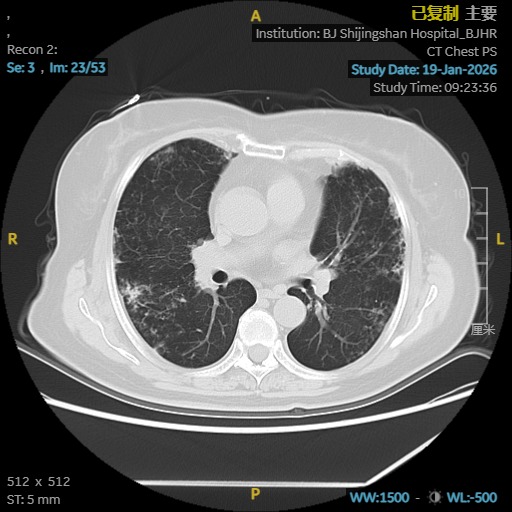

依托医院高清CT、肺功能、气管镜及精准分子检测平台,团队很快锁定了隐藏在表象背后的真实病因:鸟胞内分枝杆菌合并耐药念珠菌感染,同时伴有进展性肺间质纤维化。这两种疾病相互交织,诊治难度大,对医疗团队提出了很高要求。

为给患者制定最安全有效的治疗方案,马霞主任医师立即启动MDT机制,联合临床药师、影像科、检验科专家进行会诊。在多学科共同研判下,团队为栗女士量身定制了集抗感染、抗真菌、抗纤维化于一体的综合治疗策略,在精准打击病原的同时,全力保护肺功能。

A影像学证据:胸部高分辨率CT(HRCT)显示存在肺纤维化表现,如网格影、蜂窝影、牵拉性支气管扩张等,且排除特发性肺纤维化(IPF)。